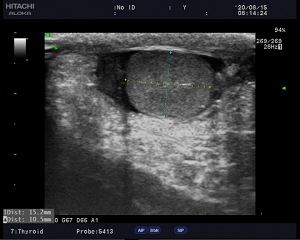

看到报告结论后,这位母亲长舒一口气,紧皱的眉头慢慢放松,不停的对医生说着谢谢。与此同时我科值班医生马上联系外科值班医生,沟通情况,经临床医生触诊等,综合考虑为附睾炎,经过一系列治疗后,于当晚23:20和次日的8:20进行密切复查,诊断结论为:左侧附睾体积增大,血流信号丰富,附睾炎。

(8月15日,转向有所好转,搞完可见血流信号)